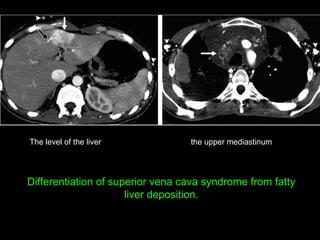

the upper mediastinum The level of the liver Differentiation of superior vena cava syndrome from fatty liver deposition.

the upper mediastinumThe level of the liver Differentiation of superior vena cava syndrome from fatty liver deposition.